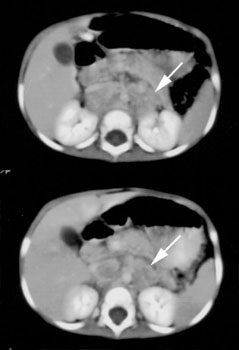

Neuroblastoma: Bone scan and MIBG exam. Diffuse skeletal metastases are evident on bone scan, but are more clearly revealed on the MIBG exam. Uptake within the patients primary lesion (CT center white arrows) can also be seen on the MIBG exam. A plain film skeletal survey demonstrated a very subtle periosteal reaction within the distal left femoral metaphysis, but was otherwise normal (Click plain film to enlarge) |